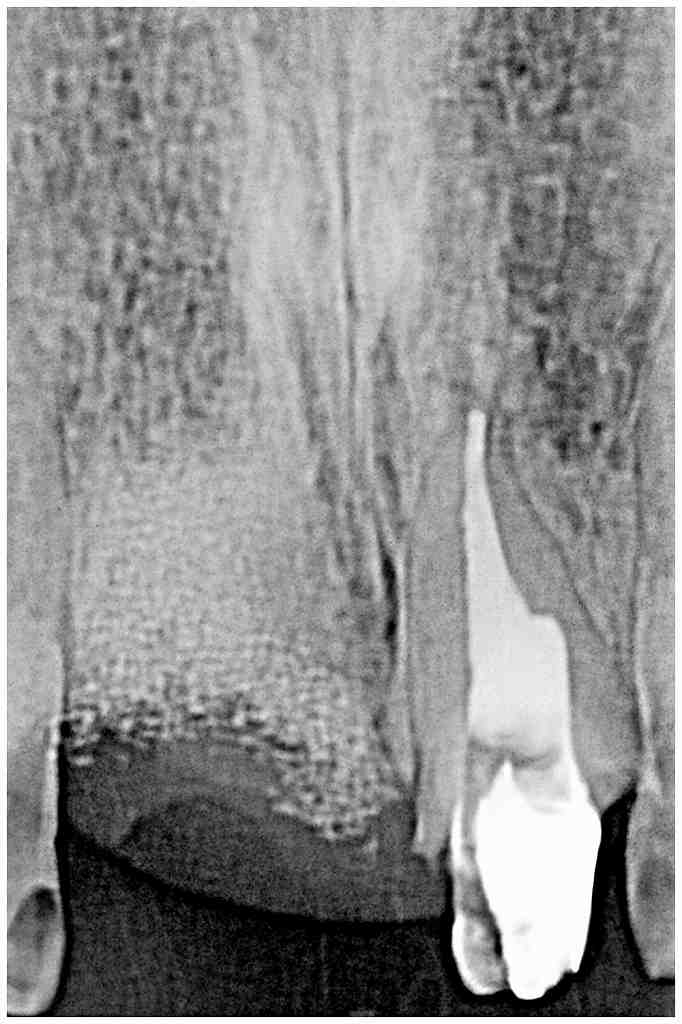

この歯は抜歯させていただきました

骨補填材を転入し、ソケットプリザベーションを一応行っていきました

今回はアパタイト顆粒を転入しています

ブリッジになっても骨の目減りが少なくて済むからです